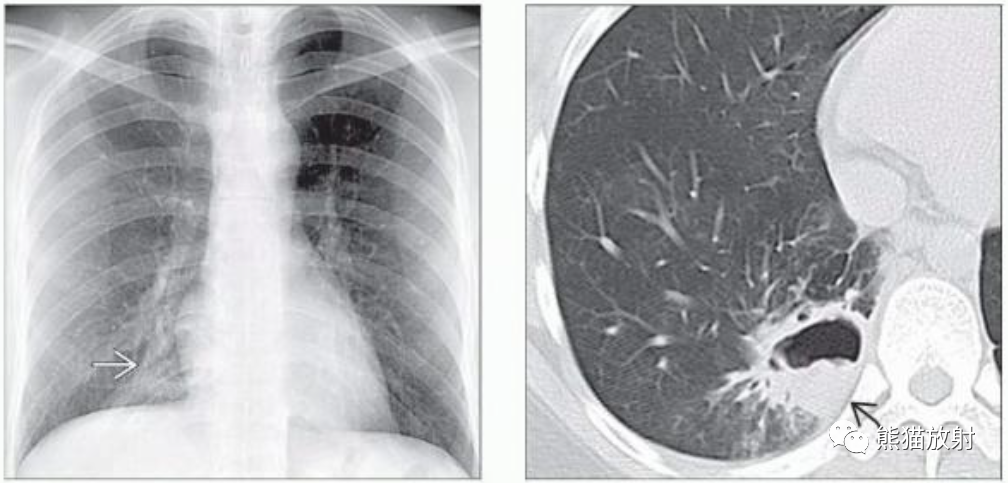

(左)免疫功能低下的肺隐球菌病患者,PA胸片显示右下肺野见一空洞性肿块,内见气液平面。

(右)同一患者,CECT肺窗和软组织窗图像显示右肺下叶空洞性肿块,内见气液平面,提示脓肿形成。邻近肺实质可见片状磨玻璃影(弯箭)。